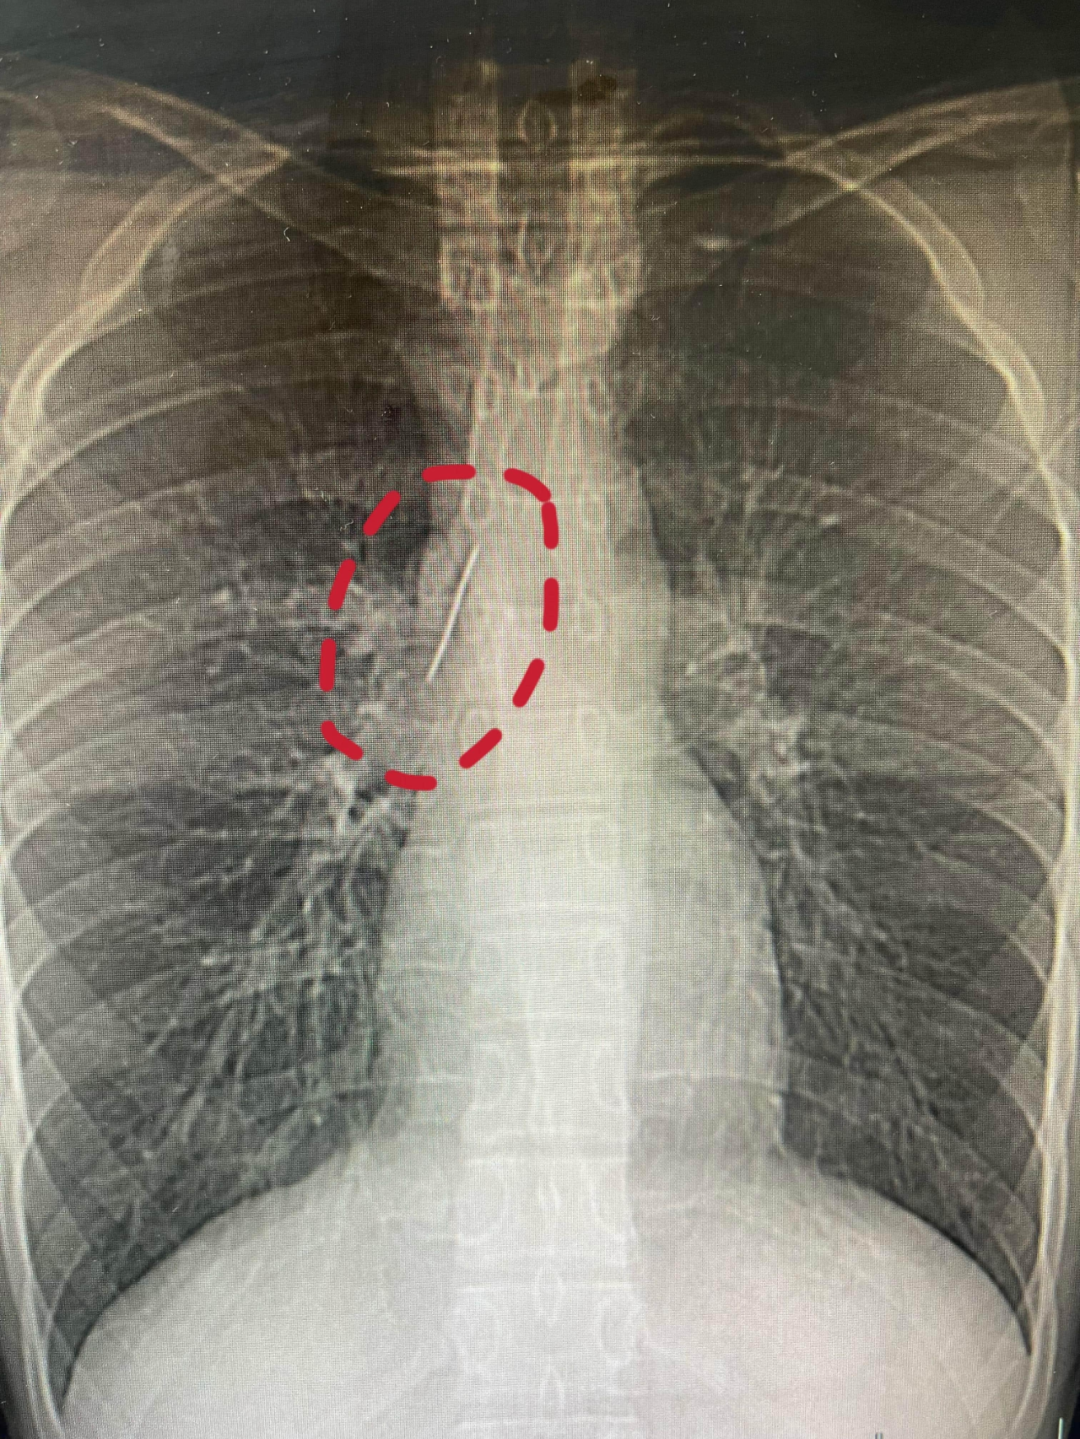

不久前,怀揣军旅梦的他,满怀期待参加征兵体检,没想到胸片结果让医生当场警觉:他的胸腔内有一处明显金属高密度影,形态细长,像一根针。

进一步CT检查确认,异物像是一根金属针,斜插在肺组织内,针尖紧紧贴着胸主动脉、上腔静脉等体内重要血管,稍有位移就可能刺破血管引发致命大出血。

面对检查结果,小陆和父母都懵了。这根针从哪来?为何在体内藏了这么久?更让人诧异的是,针体已刺入肺实质,却没有造成气胸、血胸,没有感染发炎,小陆平时跑跳、运动都毫无异常,从未出现胸闷、胸痛、咳血等症状。小陆父母反复回忆,终于想起十多年,小陆曾莫名长时间哭闹不止,当时没找到原因,也没往异物上想,大概率就是那次意外,针被不慎扎入体内。